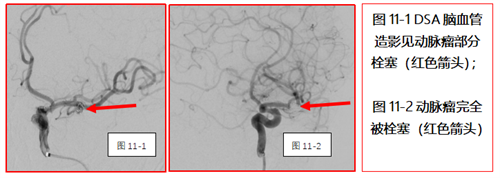

脑血管检查发现左侧大脑中动脉

局部瘤样膨出(动脉瘤)并破裂出血。

当天凌晨急诊介入手术,栓塞出血的动脉瘤

避免出血进一步增多,挽救了患者生命。